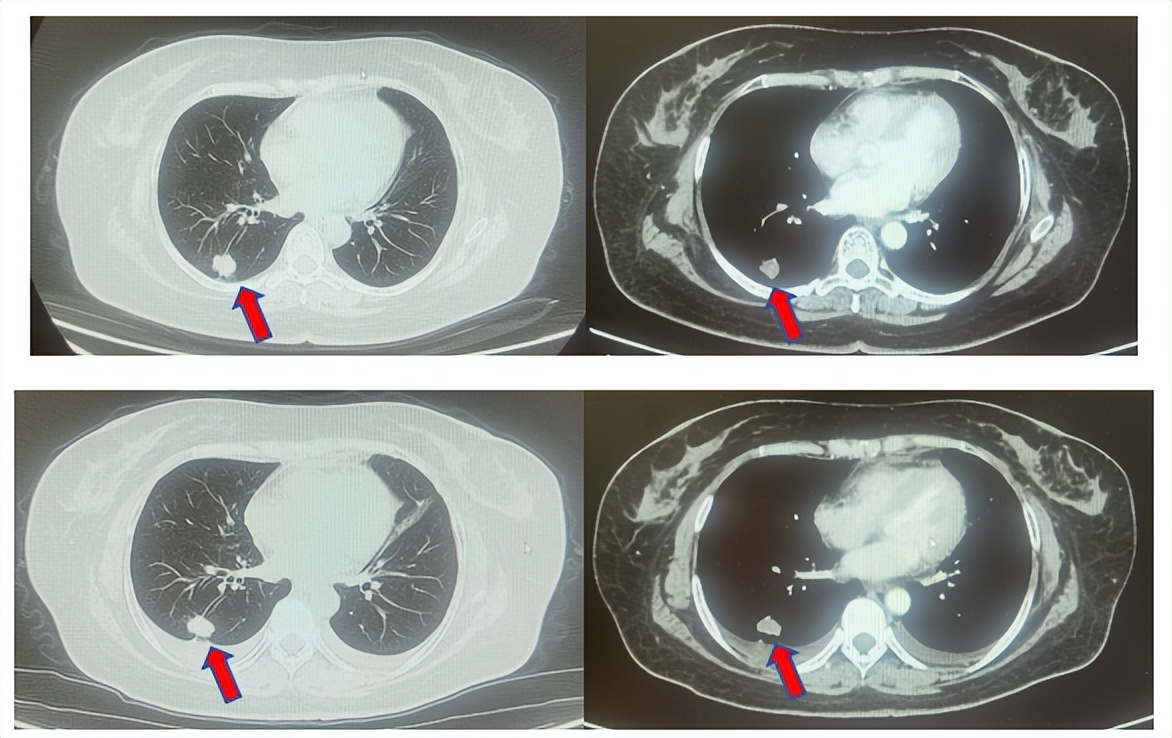

2.2影像学检查(图5)

肺+全腹CT增强:右肺中叶肿块,考虑恶性,双肺胸膜下炎症,双侧胸膜局限性增厚,右侧锁骨上淋巴结增大,纵隔淋巴结稍大;

颈部CT增强:右侧锁骨上及右颈部、纵隔多发淋巴结肿大。

脑MRI增强:头MR平扫+增强未见确切异常。

骨ECT:正常骨相(定期复查)。

图5:上两图分别展示基线时肺CT肺窗及纵隔窗右肺中叶病灶影像,下两图表示基线状态时纵隔淋巴结及锁骨上淋巴结影像。